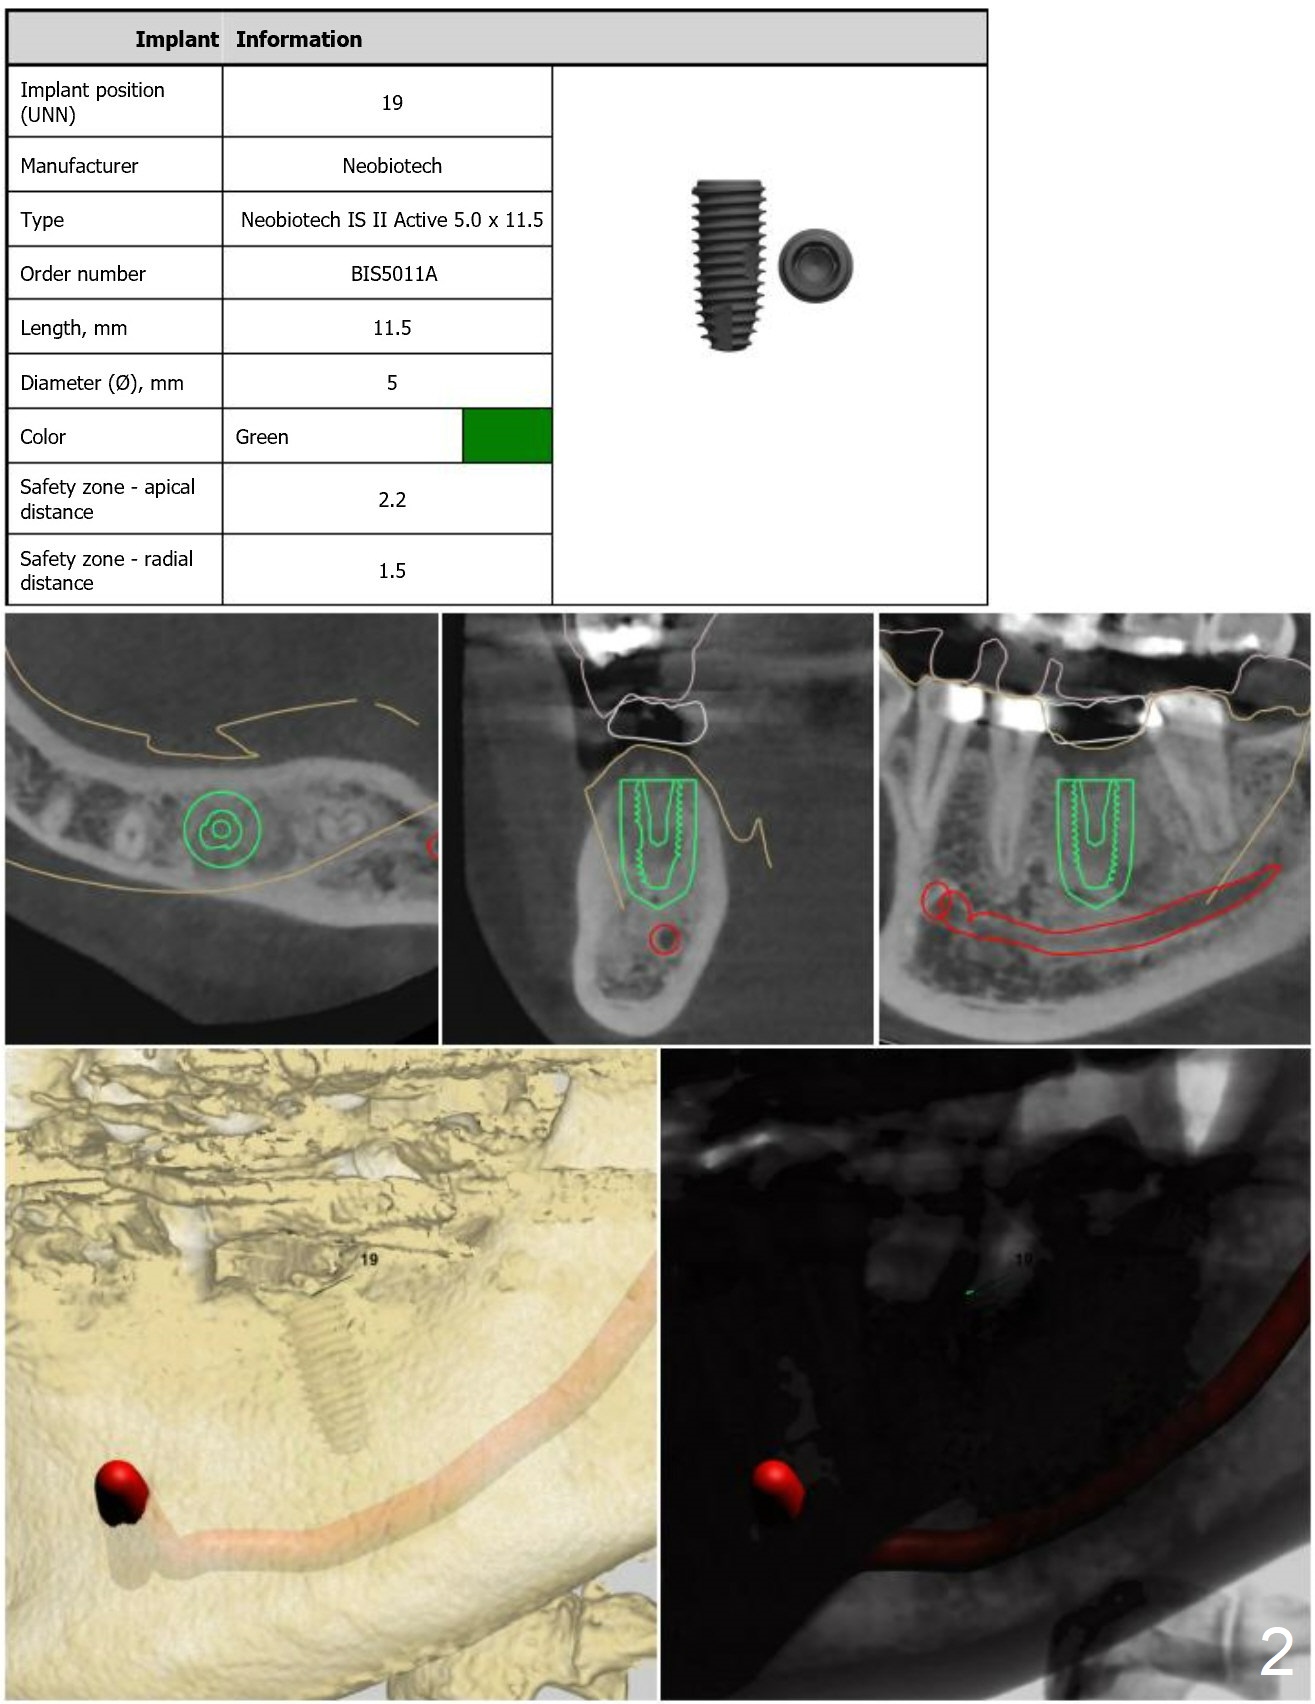

Implant Length/Mouth Opening

Although the woman is short, her bone at #19 is long enough for 11.5 mm implant (Fig.5). If her mouth opening is limited, the last drill will be 10 mm (Fig.6).